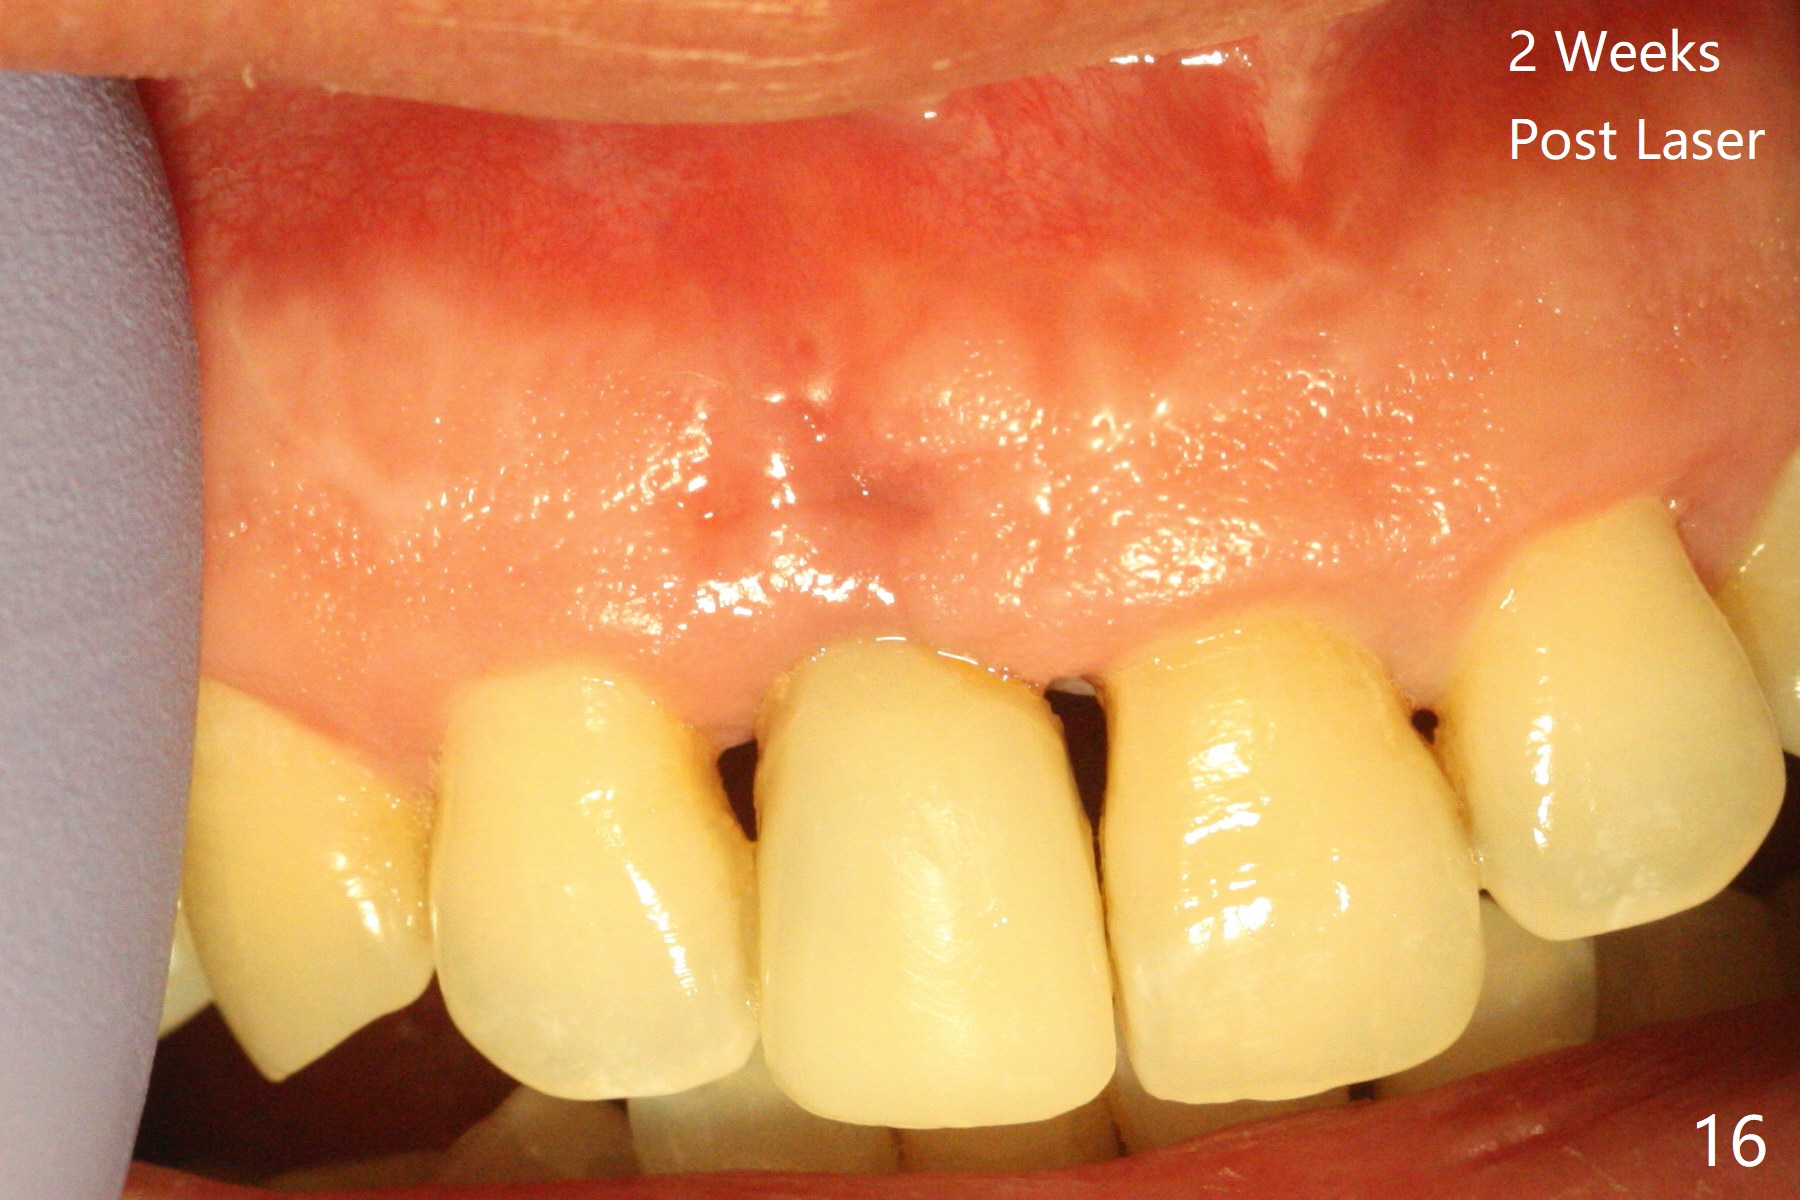

The patient returns because of purulent exudate from the buccal fistula (Fig.1 *) 1 year 9 months postop (1 year 3 months post cementation). Preop CT shows buccal thread exposure (Fig.2 arrowheads). To prevent postop gingival recession, a semilunar incision is made between the fistula and the gingival margin (Fig.3). After removal of granulation tissue (Fig.4), allograft in sticky bone form is packed (Fig.5). Following placement of PRF membrane and 6-month collagen membrane, the wound is closed (Fig.6). Since the implant (Fig.7 I) thread exposure is within bone (B) boundary (Fig.8 red dashed line), bone graft with PRF should be able to take care of periimplantitis (A: abutment). To prevent periimplantitis in similar situation, the immediate implant should be placed deep (not necessarily long, 18 mm) and narrower (3.5 mm instead of 3.8 mm). The defective buccal plate should be repaired with sticky bone and collagen membrane with incision if necessary. The wound does not dehisce 1 week postop (Fig.9) or 3 weeks postop (Fig.10, immediately post suture removal). Although bone graft seems to stay in place 6 months postop (Fig.11,12), the patient complains of bone graft expulsion sometimes. The buccal gingiva has deficiency (Fig.13). To fix it, make a remote incision (Fig.14 black line) and dissect before gingiva graft (Fig.15 dashed line). After removal of crown/abutment, the sinus track and implant surface are treated with Waterlase. A shorter cuff abutment is placed (4.5x5(4 to 3) mm) with a new provisional. The patient feels better with reduced sinus track 2 weeks postop (Fig.16).